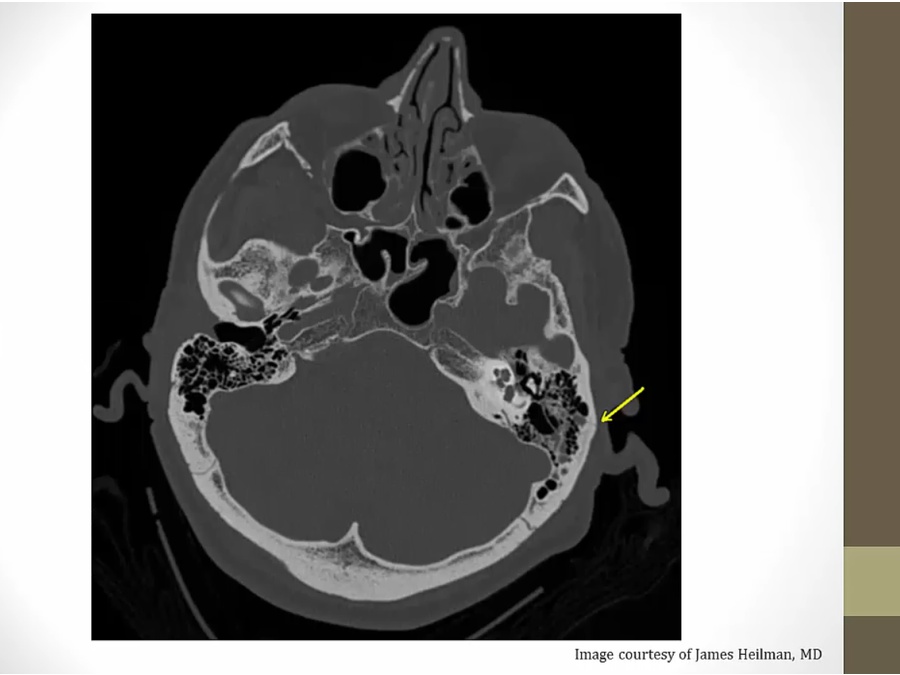

Bleeding

IVH